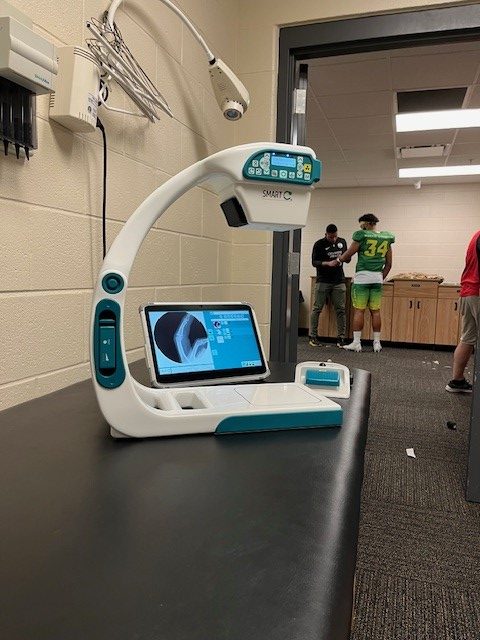

In sports medicine, the ability to quickly and accurately diagnose injuries is crucial for effective treatment and recovery. SMART-C® utilizes fluoroscopy to provide real-time imaging at the point-of-care, setting it apart from traditional X-ray systems that only provide static radiography.

This article delves into five common sports injuries, providing detailed clinical insights and explaining why the SMART-C® is the superior option for point-of-care imaging.

The SMART-C’s fluoroscopic imaging delivers high-resolution, real-time visualization of fractures, which is essential for assessing their morphology, displacement, and involvement of adjacent structures. Unlike traditional x-ray systems that provide only a static image, the SMART-C® allows for a dynamic assessment, capturing images from multiple angles to provide a comprehensive view. For example, in a spiral fracture, the SMART-C can reveal many aspects of the fracture by assessing shortening, angulation, malrotation, and translation, aiding in precise reduction and surgical planning. The ability to have SMART-C® at the point-of-care for immediate on-site imaging reduces delays in diagnosis and treatment, which is critical for optimal patient-centric recovery.

SMART-C® offers detailed fluoroscopic images that accurately depict the spatial relationship of dislocated bones and any associated fractures. Its portability allows for immediate, on-site imaging, which is crucial for prompt reduction procedures. With the SMART-C®, real-time imaging can guide the reduction process and confirm successful relocation, reducing pain and preventing further injury.

The SMART-C®’s fluoroscopic imaging is highly sensitive in detecting stress fractures. Traditional x-rays often miss these subtle changes due to their static nature. The SMART-C® provides dynamic, real-time imaging, allowing for a more detailed and comprehensive assessment. This capability enables early diagnosis and timely intervention, such as rest and activity modification, preventing further damage and facilitating quicker recovery.

SMART-C® provides high-definition fluoroscopic images crucial for evaluating intricate fractures such as scaphoid or distal radius fractures. Unlike traditional x-rays that offer a single static view, the SMART-C’s ability to perform multiplanar imaging ensures a thorough assessment of fracture patterns and associated soft tissue injuries. For example, in scaphoid fractures, the super fine resolution (99-micron pixel size) of SMART-C® enables physicians to detect subtle fractures that traditional x-rays might miss, allowing for early and appropriate treatment to prevent non-union and other long-term complications.

The SMART-C’s fluoroscopy provides dynamic, high-resolution images of the ankle joint, enabling detailed assessment of fracture lines, displacement, and joint congruency. Traditional x-ray systems provide static images, which can be limiting. The SMART-C’s portability ensures immediate on-site imaging, crucial for early intervention. In trimalleolar fractures, for example, the SMART-C can guide reduction and stabilization procedures, ensuring proper alignment and minimizing complications.

The SMART-C® revolutionizes sports medicine by offering immediate, high-quality fluoroscopic imaging essential for diagnosing and managing osseous injuries. Its portability, ease of use, and advanced imaging capabilities make it a superior option compared to traditional x-ray systems that provide only static radiography.

The SMART-C® revolutionizes sports medicine by offering immediate, high-quality fluoroscopic imaging essential for diagnosing and managing osseous injuries. Its portability, ease of use, and advanced imaging capabilities make it a superior option compared to traditional x-ray systems that provide only static radiography.

Whether physicians are using the SMART-C® and tablet at the point-of-care or mounted on the support stand in a medical room, they have the flexibility to acquire sharp motion images at the exact angle needed, to properly treat their athletes. By facilitating prompt and precise assessment of bone fractures, dislocations, stress fractures, wrist and hand injuries, and ankle fractures, the SMART-C® significantly enhances the management and recovery of sports-related injuries.

The SMART-C® revolutionizes sports medicine by offering immediate, high-quality fluoroscopic imaging essential for diagnosing and managing osseous injuries. Its portability, ease of use, and advanced imaging capabilities make it a superior option compared to traditional x-ray systems that provide only static radiography.

The SMART-C® revolutionizes sports medicine by offering immediate, high-quality fluoroscopic imaging essential for diagnosing and managing osseous injuries. Its portability, ease of use, and advanced imaging capabilities make it a superior option compared to traditional x-ray systems that provide only static radiography.